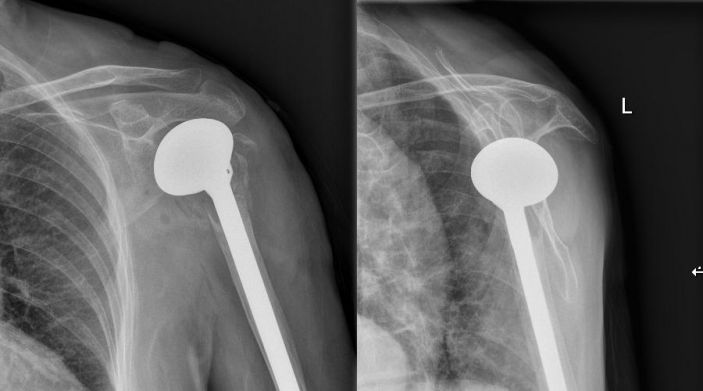

吳主任根據CT+三維重建先行拟訂詳細的手術方案。9月4日在經過充分的術前準備後,老太太被送進了層流淨化手術室,行左側人工肱骨頭置換術。家屬在手術室外焦急地等待,而此時手術室内的吳志斌主任在麻醉科的配合下,根據方案有條不紊地開展手術,娴熟地取出左肱骨頭,并給予安裝肱骨假體,考慮到患者骨質疏松明顯,吳主任還特地加用了骨水泥。術中老太太未出現血壓下降及意識改變等其他不适,整個手術非常順利,再次給患者家屬滿意的答卷。經過醫護人員的對症治療、精心護理,老太太将于近日康複出院。

△術後